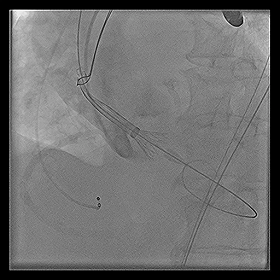

◆2015年1月17日行TAVI术。

◆植入29mm CoreValve人工支架瓣膜一枚。

术后症状明显缓解,近一年未因心衰住院;

一年期复查心超,未见主动脉瓣狭窄和关闭不全。